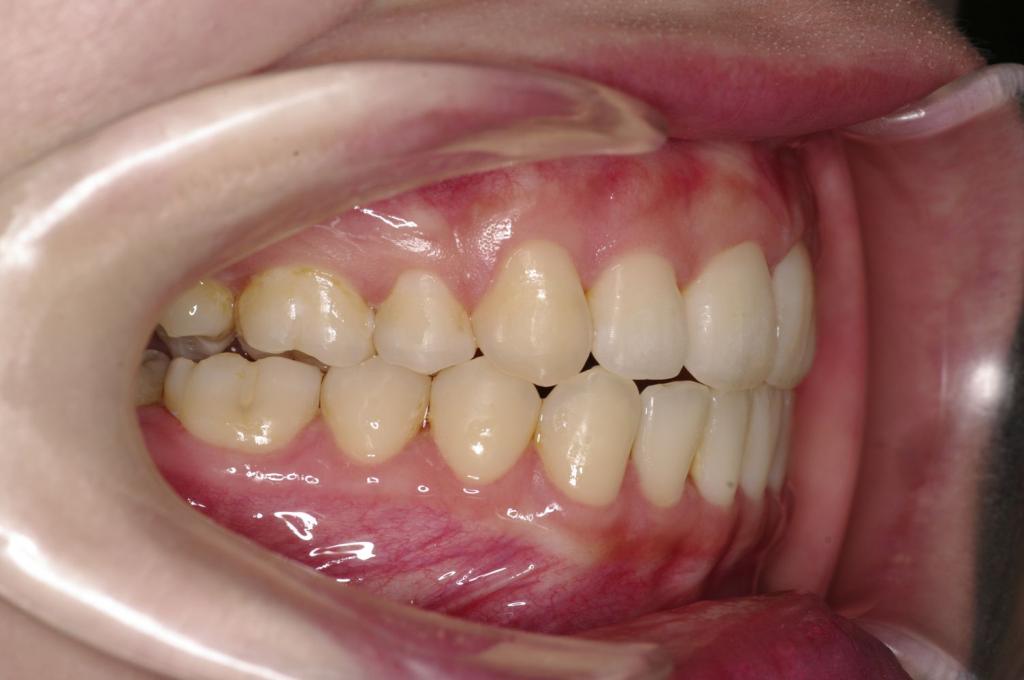

前歯、出っ歯・開咬の矯正治療

(治療期間、治療前後写真、治療方法、費用)WORKS